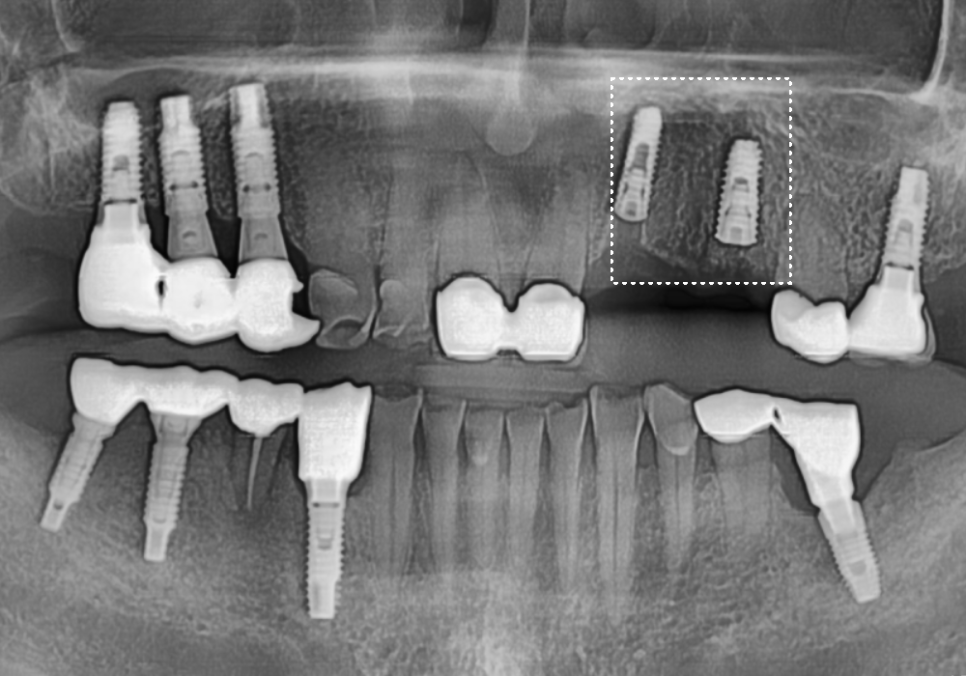

240202

그 후 4개월이 지나, 임플란트 뿌리와 뼈가

단단하게 굳은 것을 확인한 뒤,

지르코니아로 보철물을 올려드려

치료를 마무리했습니다.

240321